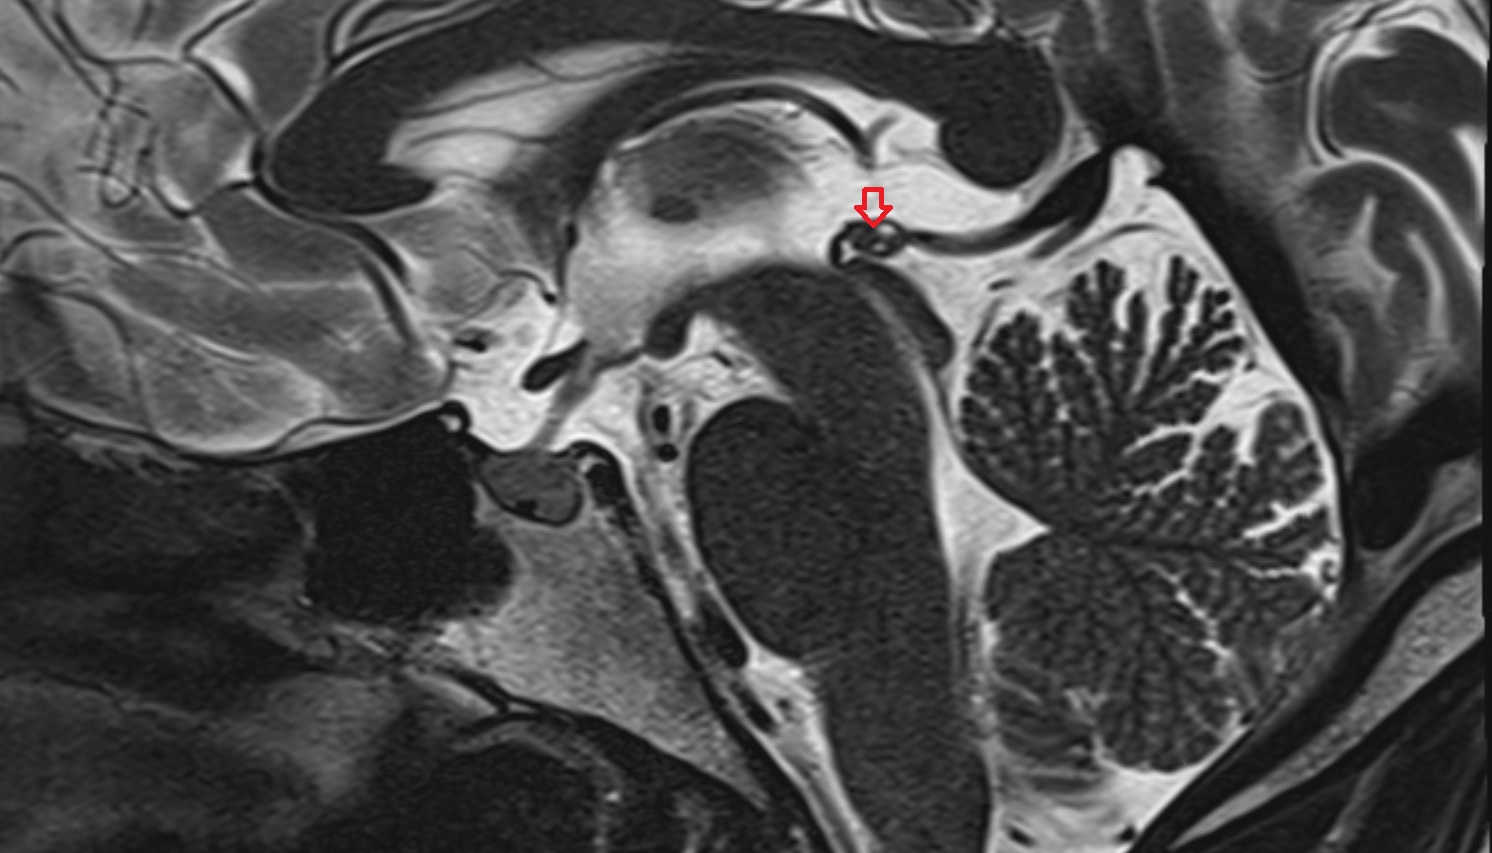

- Cerebral aqueduct

- Superior opening of cerebral aqueduct